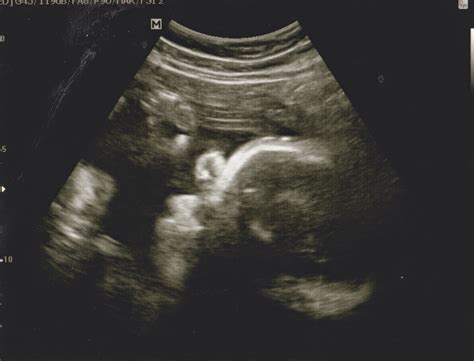

The experience of a 32 week ultrasound is very similar to your previous scans. You will typically be asked to lie on an examination table, and a sonographer will apply a cool, water-based gel to your abdomen. The sonographer then uses a transducer—a handheld device that emits sound waves—to capture images of your baby on a monitor.

Because your baby is now larger and there is less amniotic fluid relative to the baby’s size compared to the second trimester, the images may look a bit different. You might notice your baby's features more clearly, such as the face, limbs, and movements. It is an excellent time to witness your baby practicing breathing movements, sucking their thumb, or even yawning.

Fetal Biometry Measuring the head circumference, abdominal circumference, and femur length to estimate weight.